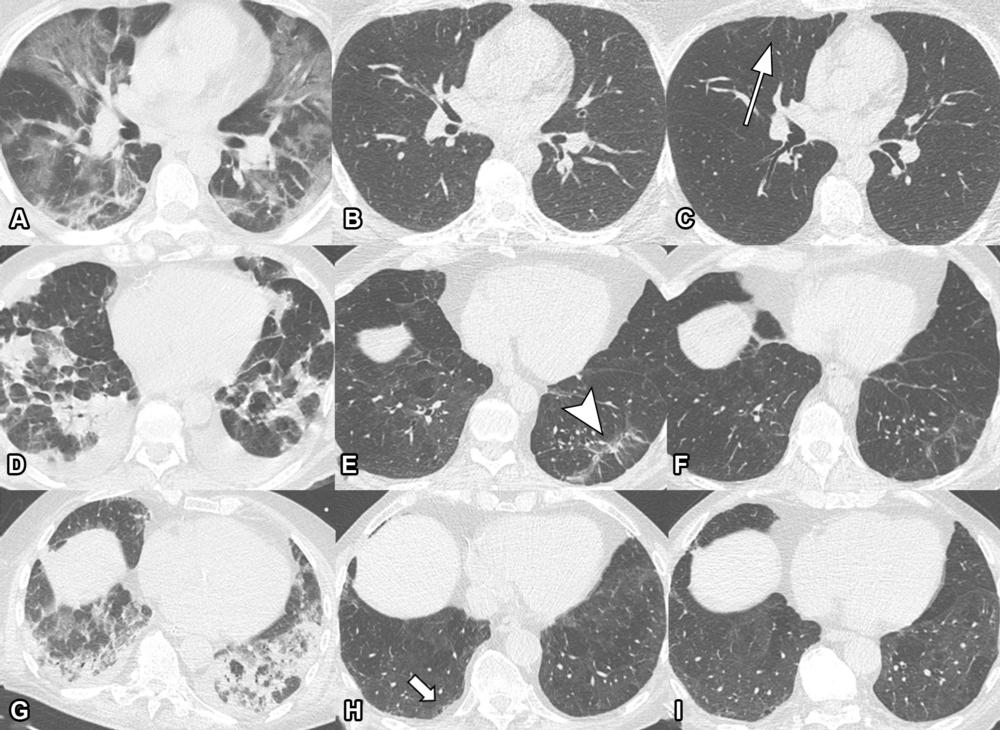

Figure 4. Serial non-contrast axial chest CTs of three study participants with prior COVID-19 pneumonia. Chest CT of a 44-year-old man (upper row, A-C) displayed extensive bilateral GGO and supleural reticulation during acute COVID-19 (A). At the 2-month follow-up almost complete resolution of GGO with residual subpleural reticulation in the middle lobe was noted (B). These subpleural reticulations (arrow) persisted up to one year after onset (C). Chest CT of a 68-year-old-man (middle row, D-F) demonstrated patchy bilateral consolidations, a subpleural arcade-like sign and pleural effusions during active infection (D). At the 2-month follow-up, a substantial improvement of OP pattern was noted with GGO and subpleural reticulation including arcade-like sign (arrowhead) in the left lower lobe (E). At the 1-year follow-up, further improvement was noticed. However, subtle reticulation and GGO could still be detected (F). Chest CT of a 79-year-old man (lower row, G-I) displayed bilateral consolidations and small areas of GGO while admitted to the ICU (G). At the 2-month follow-up, residual GGO and small subpleural microcystic changes (thick arrow) were noticed (H), which persisted up to 1 year after onset (I).